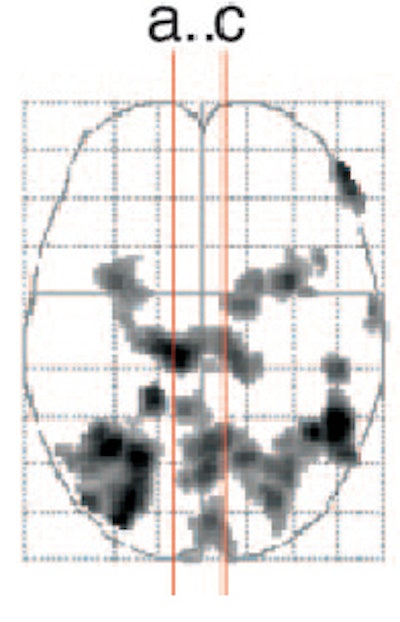

![]() |

| Regional activation maps. Activation contrast for the couples stimuli versus fixation (a-c, above) and the couples stimuli versus neutral contrast (d-f, below). Left, coronal image (a) showing greater bilateral amygdala and hypothalamic activations for males versus females for the couples versus fixation contrast. Couples versus fixation contrast for males, at the same coronal and axial views (b). The same contrast and views for females (c). |

For this study, 28 young adult, heterosexual subjects, evenly split between male and female, underwent MR scans on a 1.5-tesla Intera scanner (Philips Medical Systems, Andover, MA). First, a T1-weighted anatomical scan was done. The subjects then underwent whole-brain functional runs in order to gather blood oxygen level-dependent (BOLD) effects. The imaging protocol included echo-planar imaging and gradient recalled echo. Twenty-five 5-mm axial slices were obtained.

The data were analyzed with SPM99 software (Wellcome Department of Cognitive Neurology, University College London, U.K). The amygdala and hypothalamus were defined as the regions of interest (ROI).

According to the results, men had greater neural responses in the bilateral amygdala and hypothalamus than did women in response to images of the couples engaged in sexual activity (p<0.001). Those same images also produced greater activations in the left amygdala, and marginally greater activations in the right amygdala and hypothalamus, in men than in women (p<0.001). Additionally, men showed greater focal differential activations at a lower statistical threshold in both sides of the amygdala (p<0.005), as well as in the hypothalamus, bilateral posterior thalamus, and left hippocampus.

Finally, there was some overlap in response between the sexes, most notably in the bilateral parieto-temporal region (visual processing, somatosensory function) and the anterior cingulate (emotion, sexual motivation).